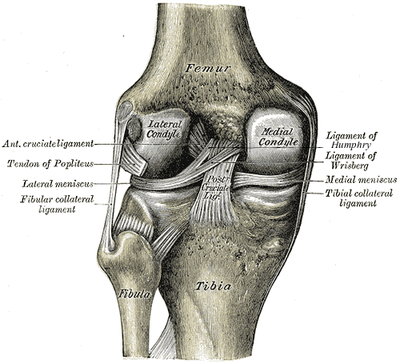

출처-https://en.wikipedia.org/wiki/Posterior_cruciate_ligament#/media/File:Gray348-2.png

무릎 관절의 뒤쪽의 해부학적 구조물은 위 그림과 같이

내측관절융기(Medial condyle), 외측관절융기(Lateral condyle), 후방십자인대(Posterior cruciate ligment), 내측반월상연골(Medial meniscus), 외측반월상연골(Lateral meniscus)이 보입니다.

내외측 측면에는 내측측부인대(Medial collateral ligment), 외측측부인대(Lateral collateral ligment)도 보입니다.